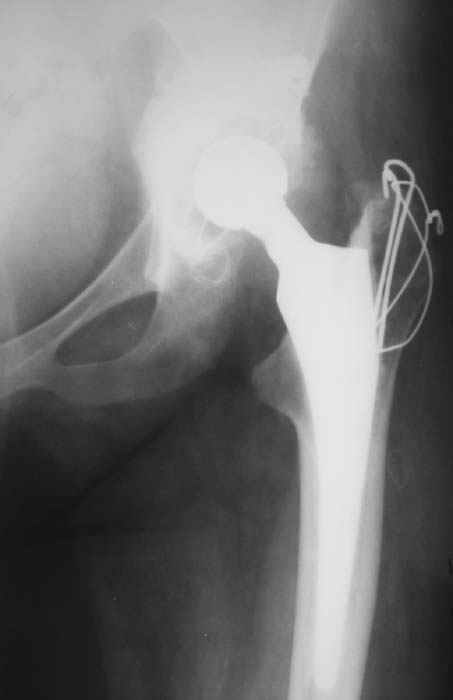

Уважаемые коллеги! Женщина, 28 лет. Страдает ревматоидным полиартритом, гормонозависима. 6 месяцев назад перенесла тотальное эндопротезирование левого тазобедренного сустава по поводу протрузионного коксита.

Использована цементная версия с пластикой дна впадины измельченной аутокостью и гранулами гидроксиапатита. Субъективное улучшение после операции. Улучшилось и стабилизировалось общее состояние. В настоящее время затруднено передвижение из-за поражения правого коленного сустава. Болезненный и <болтающийся> сустав. Предполагается замена сустава протезом без сохранения задней крестообразной связки. Возможные варианты? Заранее благодарю! С уважением,А.В.ВладзимирскийДонецкий НИИ травматологии и ортопедииДонецк, Украина

Все правильно, но я бы применил бесцементный протез. Это мнение совпадает с мнением хирургов из НИИ ревматологии. Делайте колено. АИФ.

Пациентке всего 28 лет очень рано тотальное цементное ендопротезирование.Жизнь цементной версии намного короче безцементной